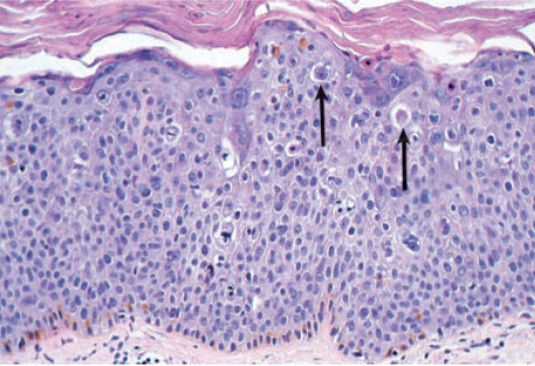

phosphatase, and bilirubin are all elevated. A liver biopsy

demonstrates alcoholic hepatitis with Mallory bodies. These

cytoplasmic structures are composed of interwoven bundles

of which of the following proteins?